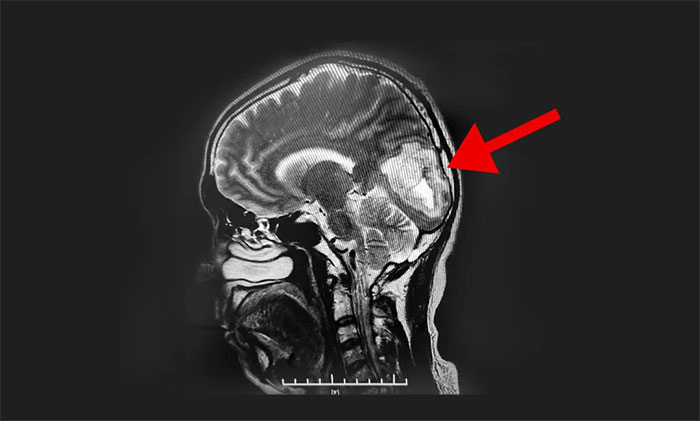

头颅MRI平扫+增强提示:左侧枕叶占位性病变。根据患者影像学检查,李士其教授、潘仁龙主任、吴治群博士会诊认为胶质瘤可能性大,并造成患者生活质量下降,应尽快行手术治疗,明确病理诊断。

▲ MR显示肿瘤超5厘米大小

经过充分术前准备后,8月23日,李士其教授在吴治群博士、黄秀夫医生协助下为患者进行了左侧枕叶肿瘤切除术。显微镜下,李士其教授根据定位,于左侧枕叶脑组织表面切开,游离脑组织,见深处有暗红色肿物,考虑为肿瘤,肿瘤质软,呈实性,血供丰富,自四周分离脑组织与肿瘤,并切除肿瘤,向右切除至大脑镰,向下、向深处切除至小脑幕,向上、向左侧切除至肿瘤边界外,在充分保护神经功能的前提下,历时约五小时,最终5公分大的肿瘤被顺利切除。